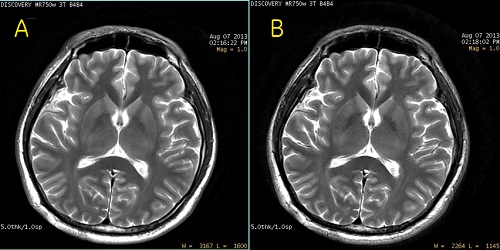

Figure 1. PROPELLER image comparison

Table 1. Image legend

NumberDescription

ATraditional PROPELLER image.

BPROPELLER image acquired with the Silent Scan package.